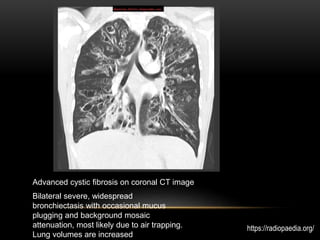

Bilateral severe, widespread

bronchiectasis with occasional mucus

plugging and background mosaic

attenuation, most likely due to air trapping.

Lung volumes are increased

Advanced cystic fibrosis on coronal CT image

https://radiopaedia.org/